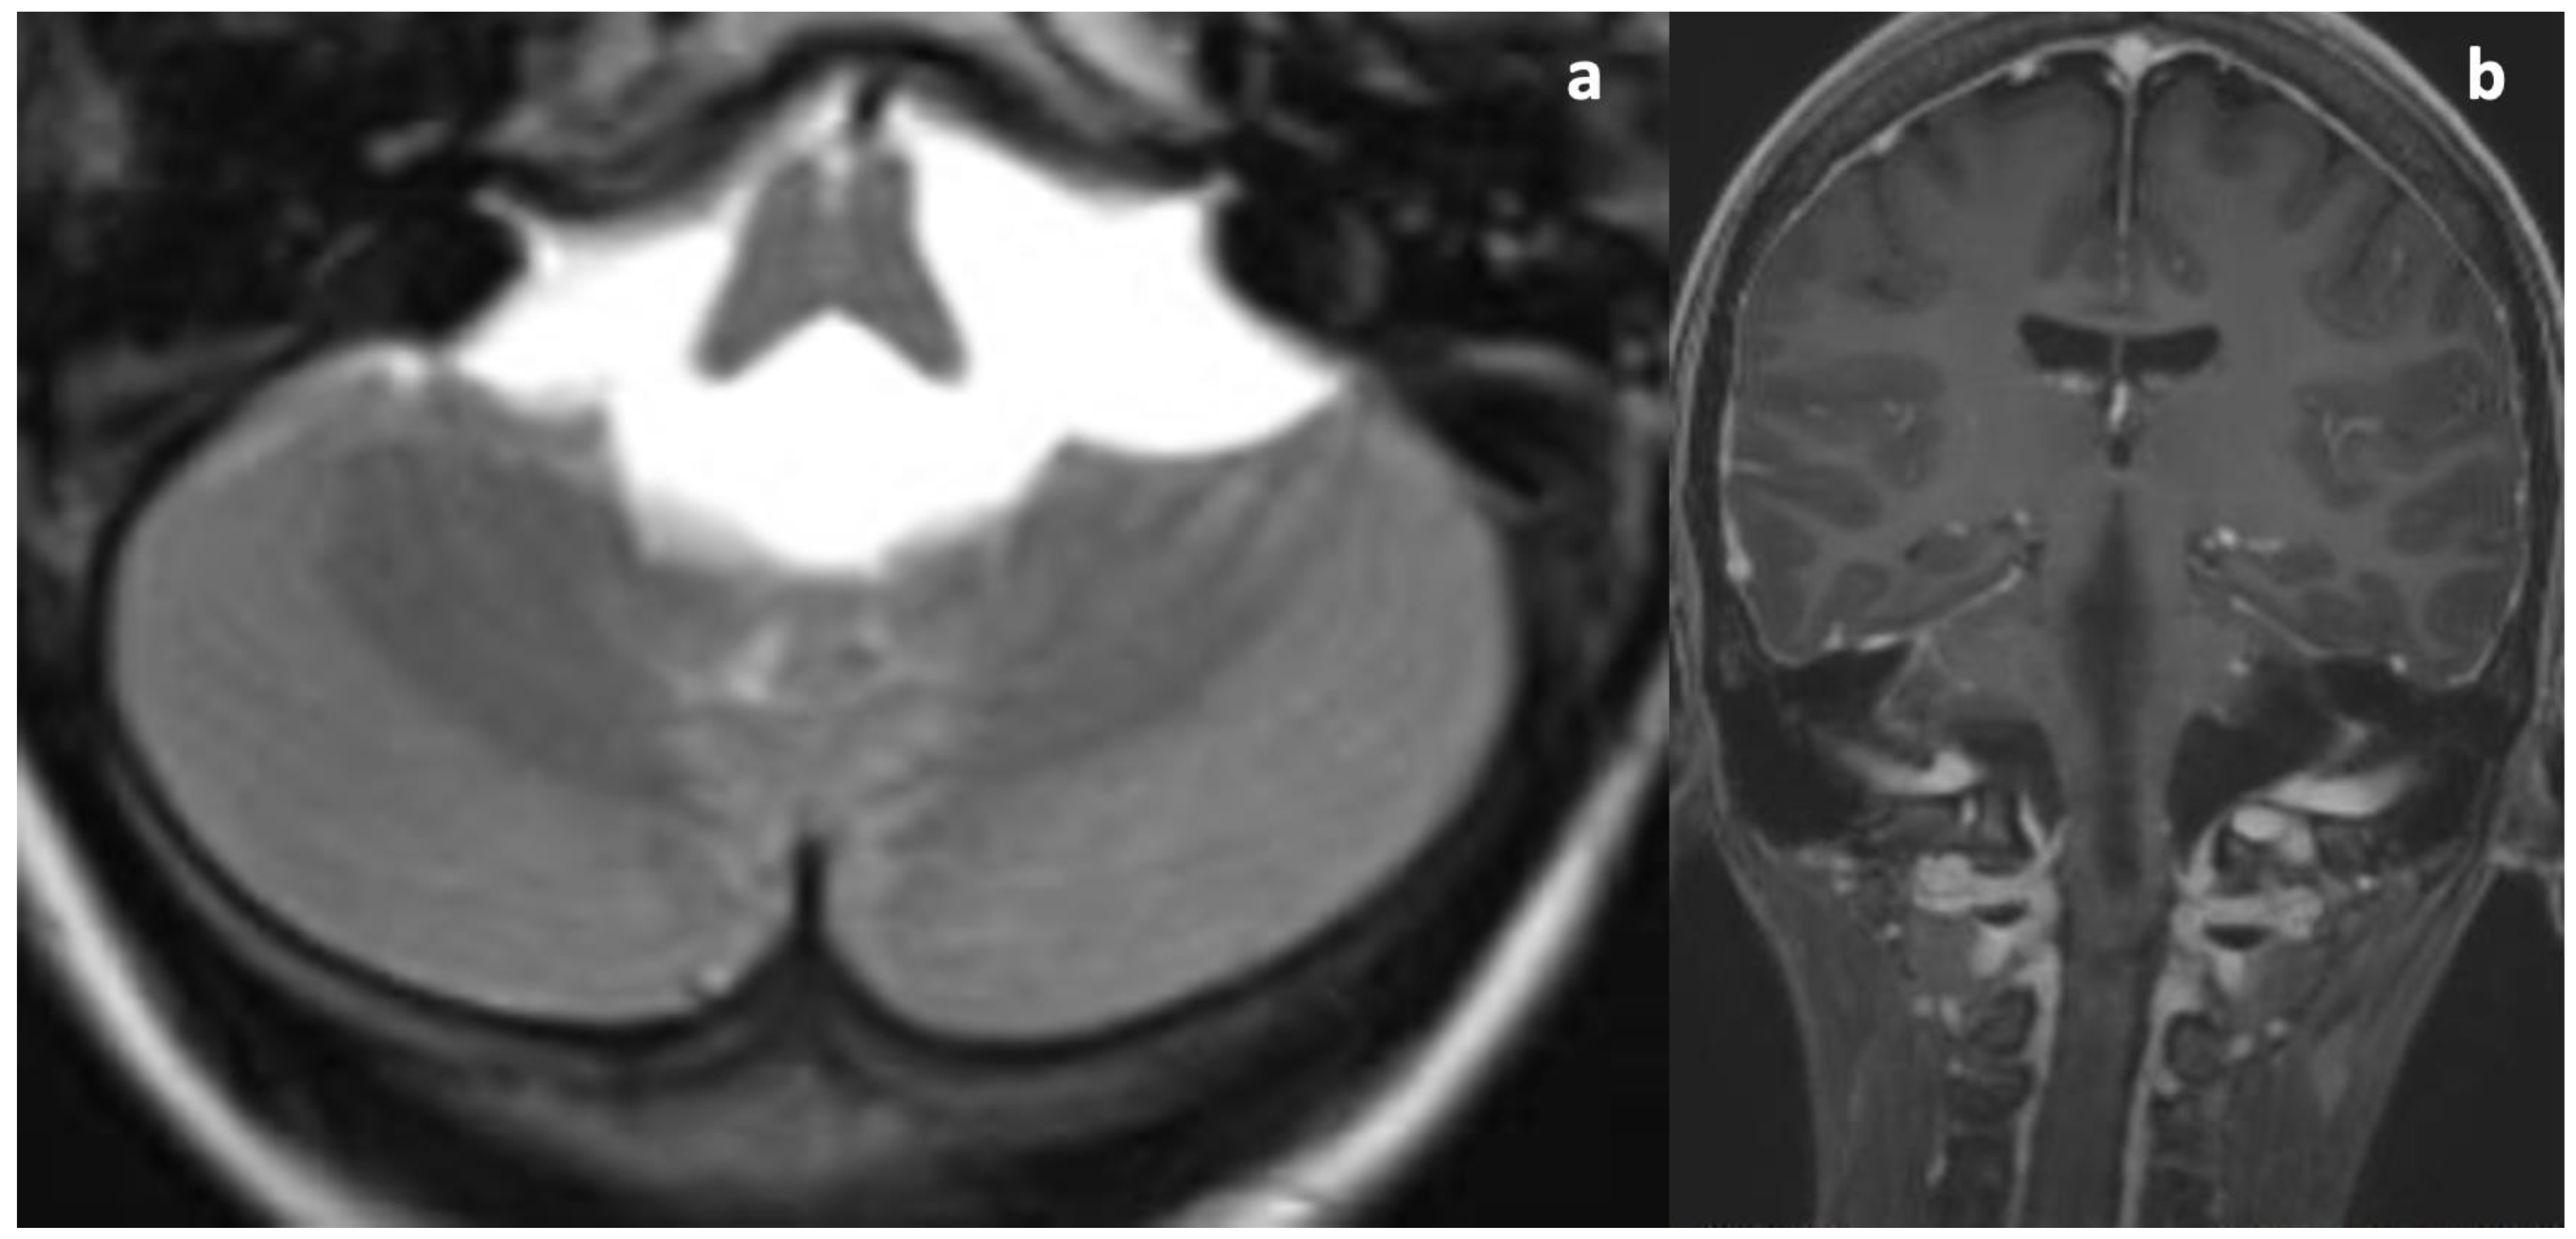

Upon her admission to our hospital, an MRI exam was repeated with contrast media administration. On T2WI, the fourth ventricle was markedly enlarged (Figure 3a and Figure 4a), compressing the pons anteriorly and the cerebellum posteriorly. Accordingly, subtentorial cisterns were effaced. A thin diaphragm was appreciable within the acqueductus Silyii. Axial scans of the enlarged fourth ventricle showed patent and enlarged foramina of Luschka (Figure 3a). T2W hyperintensities in the ventricle walls and around the cranial portion of the central canal suggested trans-ependymal reabsorption and incipient hydromyelia (Figure 4b,c). The MRI exam showed caudal dislocation of the bulbo-medullary junction and herniation of cerebellar tonsils through the foramen magnum. On the other hand, T1W C+ scans showed a diffuse enhancement of the thickened dura mater, surrounded by hyperintense epidural spaces (Figure 4b).

Figure 3. T2WI and C+T1WI upon admission. (a) Symmetrical dilatation of the foramina of Luschka. No cystic malformation or space-occupying lesion can be seen. Ventricular outlets are pervious (patient in a lying position). (b) Thickening and contrast enhancement of the dura mater; note the normal dimensions of the lateral ventricles due to the normal functioning of the TVC.